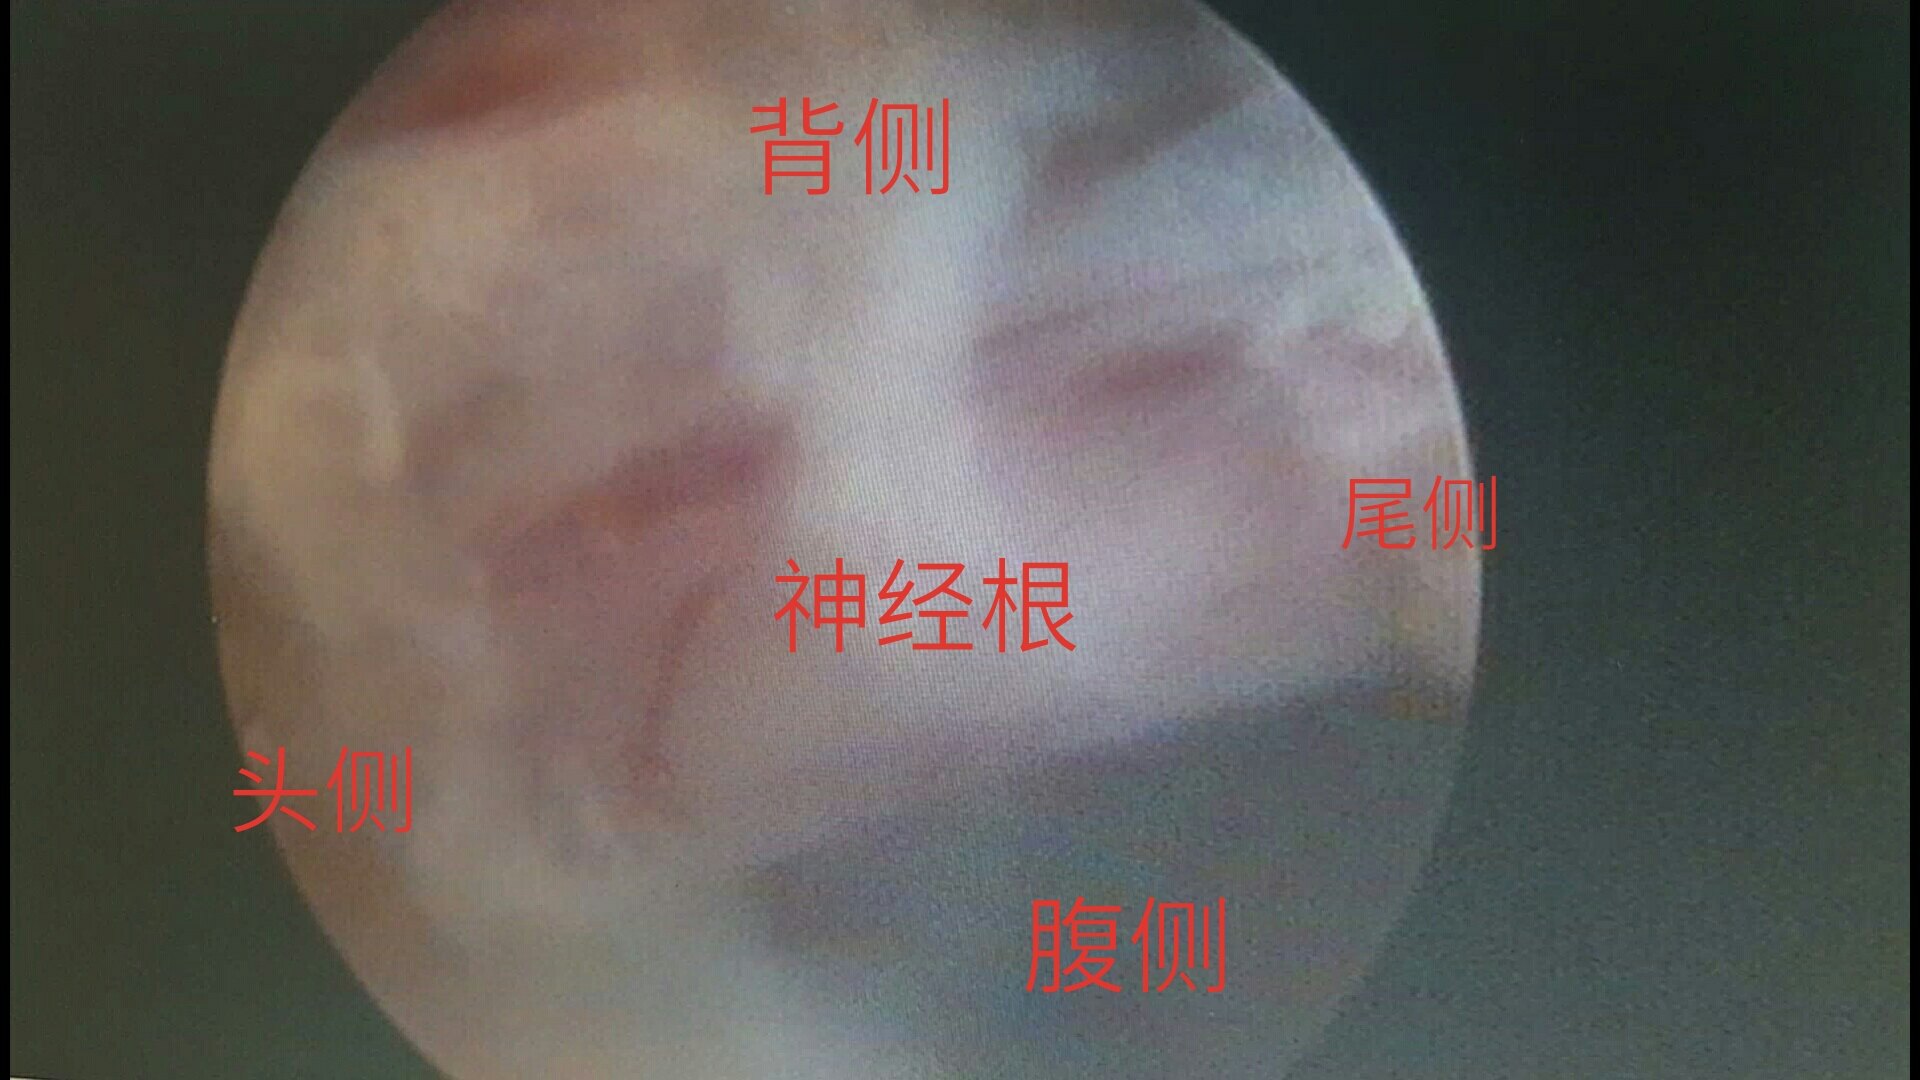

脊柱内镜翻修腰椎间盘突出症胶原酶溶核术后复

1920x1080 - 210KB - JPEG

脊柱内镜翻修腰椎间盘突出症胶原酶溶核术后复

3984x5312 - 3825KB - JPEG